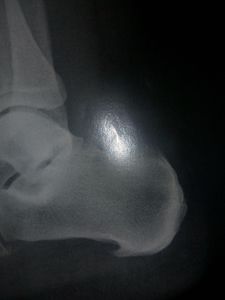

Sou Viviane Gasparetto tenho 33 anos mãe de dois filhos iniciei o sonho da casa própria devido um projeto social, dei início a minha casa mais fui diagnósticada com esporão e fascite plantar sei que não é tão grave mais requer cuidados, medicamento e a troca de todos meus calçados e com o que eu ganho não consigo fazer sei que minha saúde é importante mais como minha casa é de um projeto social tenho prazo pra construir, se alguém puder me ajudar ficarei muito agradecida pois o que eu mais quero e ter minha casinha voltar a trabalhar e dar o melhor para meus filhos Deus abençoe a todos que nunca vós falte nada